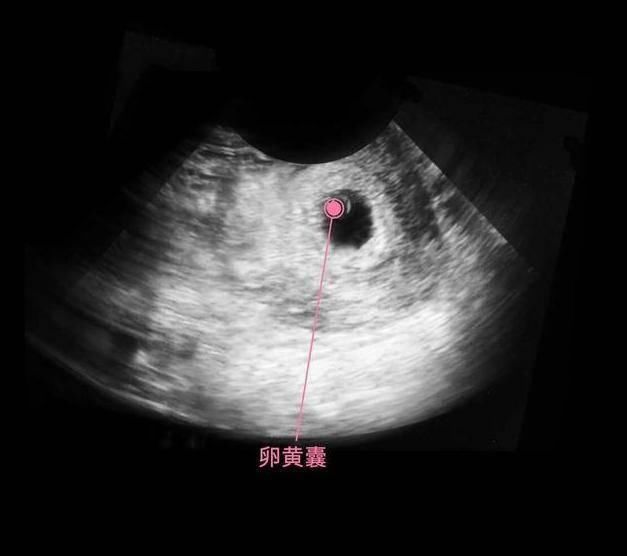

细胞继续分化,有的分化成胎儿的大脑,有的分化成胎儿的肾脏和肝脏,还有的分化成心脏等,这个时期的宝宝叫做胎芽,依靠着卵黄囊提供的营养,还用不到母体的营养呢,所以此时有了怀孕反应,没有食欲也没有关系,对胎儿发育的影响不大。